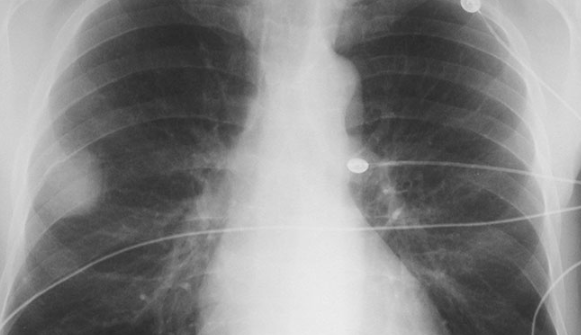

폐결절 CT 검사: 왜 반복해야 할까?

폐결절을 발견하고 나면 병원에서는 일정 주기의 폐결절 CT 추적검사를 권장합니다. 그 이유는 결절의 크기 변화, 모양의 변형, 새로운 결절의 발생 여부 등을 관찰하기 위함입니다.

CT 촬영 시 사용하는 방사선 양이 걱정될 수 있지만, 최근에는 저선량 CT가 활용되어 그 부담이 많이 줄어든 상태입니다. 방사선 노출보다 중요한 것은 결절의 진행 여부를 놓치지 않는 것이기에, 권고 일정에 맞춰 촬영을 진행하는 것이 좋습니다.

저는 6개월 간격으로 총 3회의 CT를 촬영했는데, 현재까지 결절의 크기나 모양에 변화가 없다는 소견을 받아 비교적 안정적으로 생활하고 있습니다.